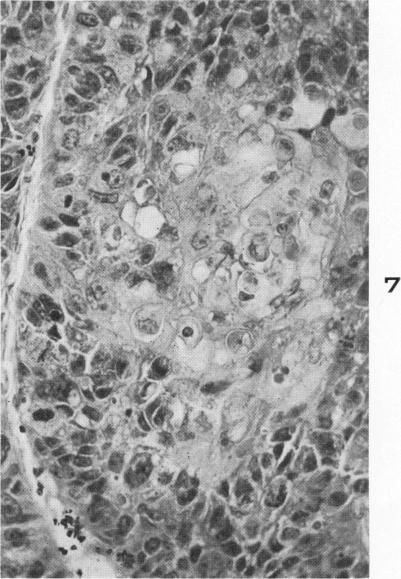

Muco-epidermoid tumors of the bronchus arising from surface epithelium.

Am J Pathol. 1958 Jul-Aug;34(4):671-83.